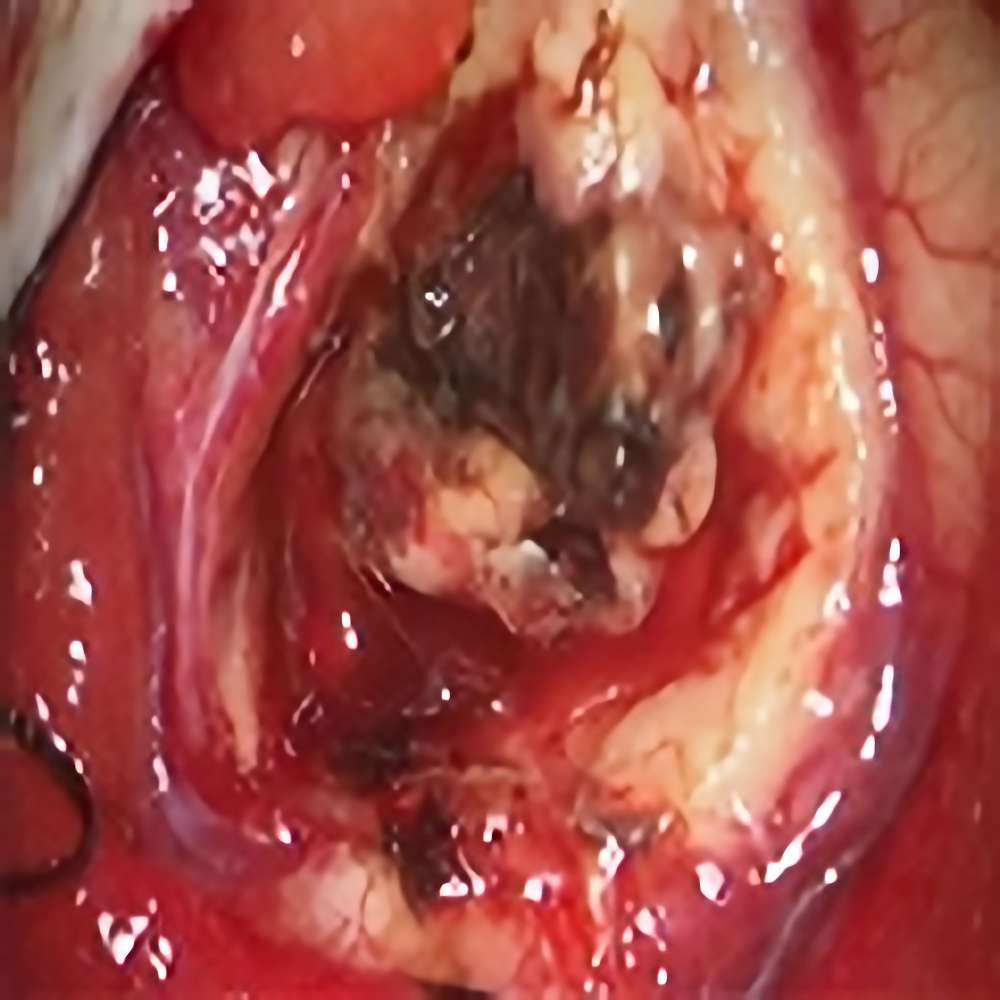

脳幹部(橋)

出血性海綿状血管腫

再出血の予防目的

大阪府の病院より紹介

Rt-supracerebellar

infratentorial

approach

No.No.52 手術前1

No.No.52 手術前2

No.No.52 手術後1

No.No.52 手術後2

CT/MRにより完全に摘出されたことが確認された